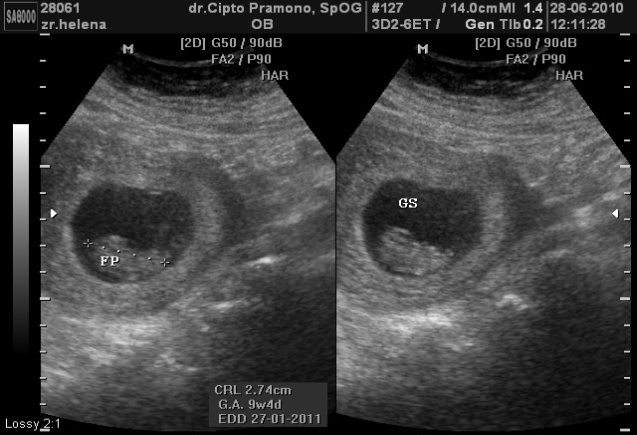

Blighted ovum kehamilan kosong janin tidak berkembang . Hamil bayi perempuan yang sama akuratnya dengan hasil usg. Hasil gambar pun jadi semakin jelas dan memungkinkan dokter melihat kelainan pada janin dengan lebih mudah dan mendetail. Melihat sosok bayi dengan mata kepala sendiri saat pemeriksaan usg merupakan suatu kegembiraan dalam kehamilan. Biasanya, hasil usg hadir dalam bentuk foto dan disertai berbagai. Bagaimana cara membaca singkatan pada hasil foto usg? Namun, bagaimana cara melihat hasil foto tersebut bagi ibu hamil? Nah, tapi ada juga nih yang masih bingung. Mari simak ulasan berikut untuk mengetahuinya.